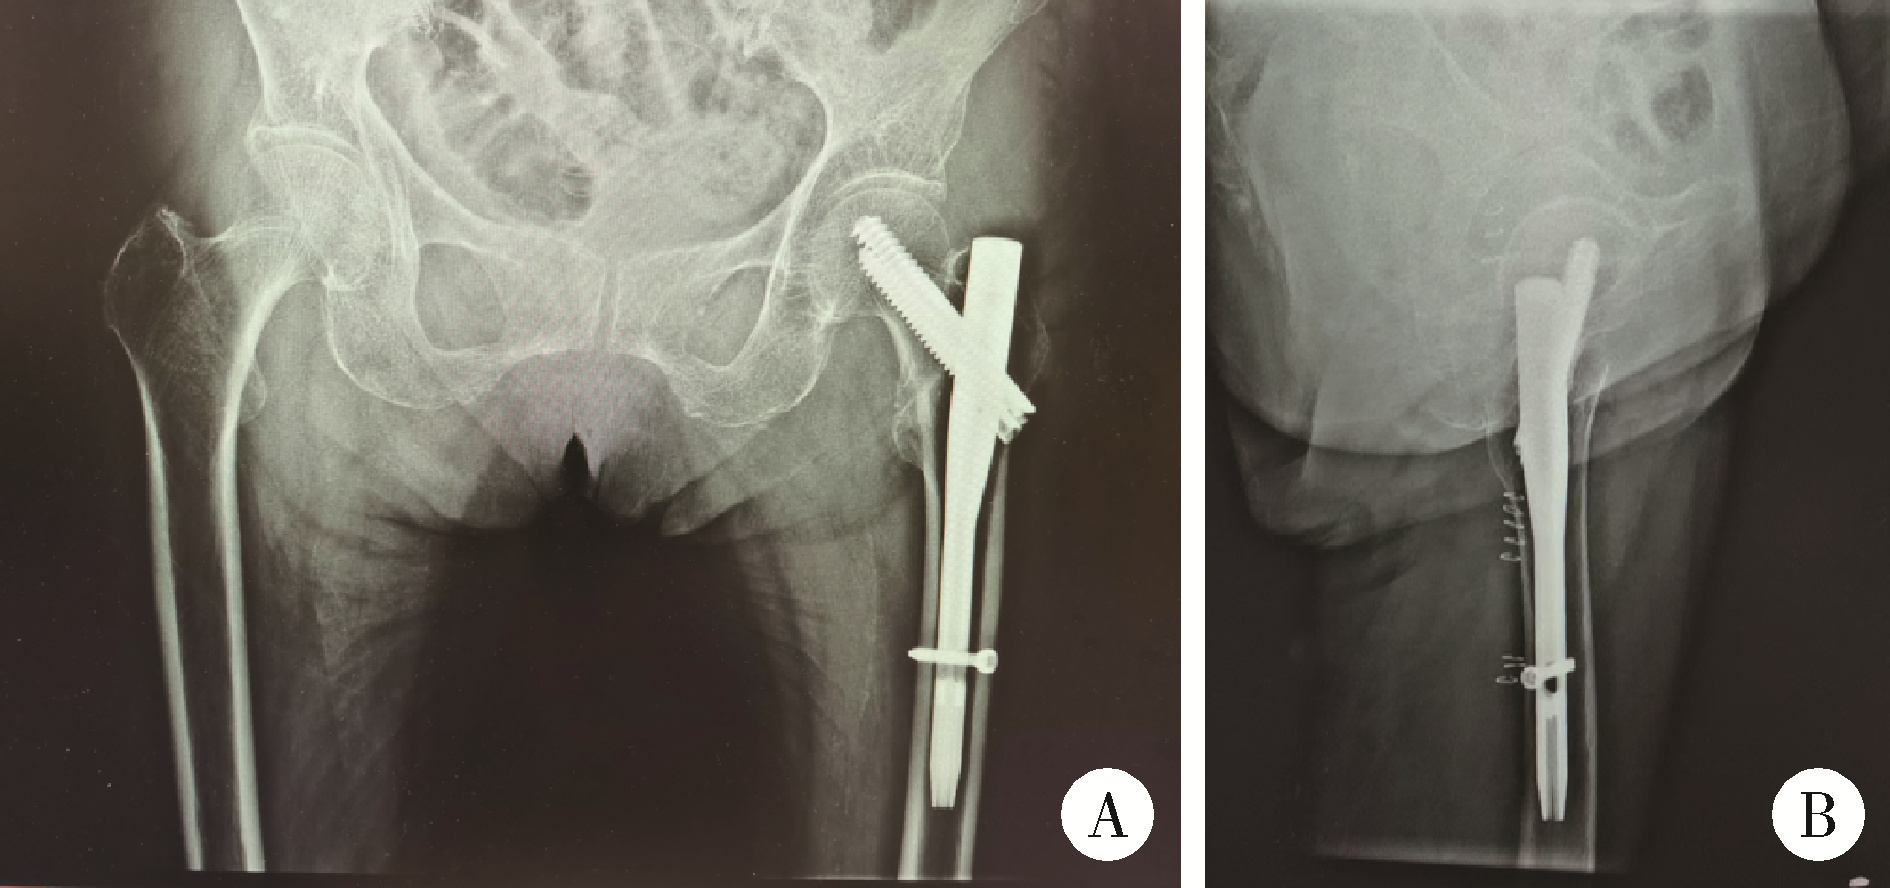

图6 患者左侧半髋关节置换术后X线片

Figure 6 X-ray films of patient after left hemiarthroplasty

A, X-ray films of both hips; B, left hip lateral view, post-left hip hemiarthroplasty.